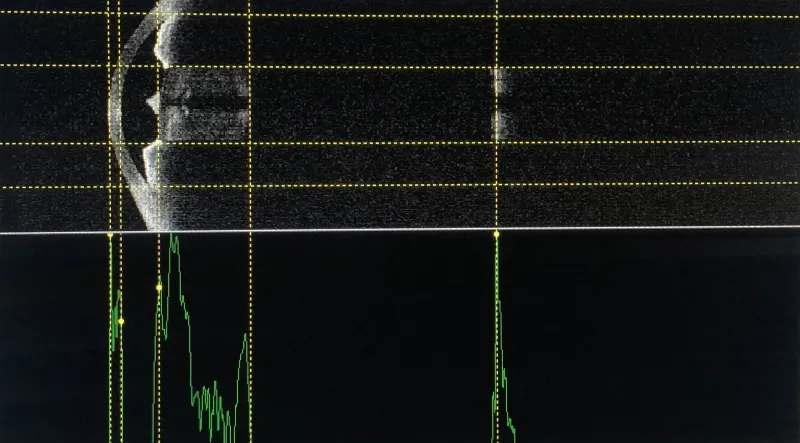

Os exames oftalmológicos desempenham um papel fundamental na avaliação da saúde ocular, sendo essenciais para diagnosticar e prevenir doenças como a catarata.

Entre os exames realizados estão testes de refração, acuidade visual, mapeamento de retina, tonometria, entre outros procedimentos que visam identificar possíveis alterações na visão.

A AORP investe em tecnologia de ponta para garantir a precisão e eficiência dos exames oftalmológicos.

Com equipamentos modernos e avançados, a clínica oferece uma gama completa de procedimentos, desde exames de rotina até avaliações mais complexas, proporcionando um diagnóstico preciso e seguro.

Os exames oftalmológicos para catarata são realizados com rigor e cuidado, permitindo uma avaliação minuciosa da condição ocular do paciente.